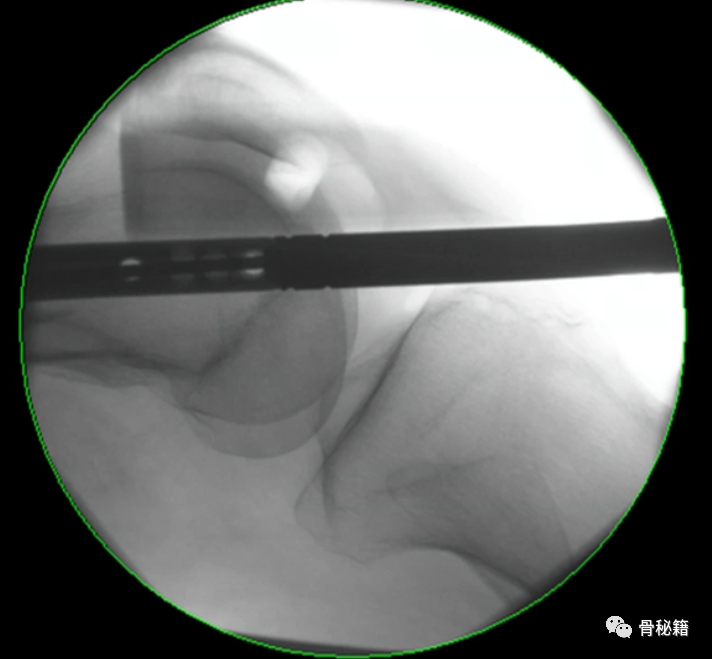

2、股骨干部复位,工具比不可少,主要是金手指

复位时注意要用一些肌松和适当的牵引

很多时候金手指不太听话这个时候可以试试顺时针和逆时针旋转